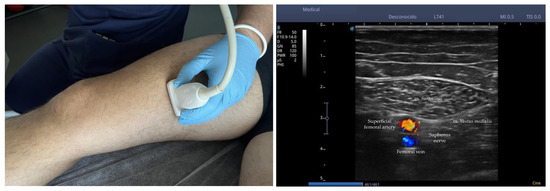

PENS was administered using the ES-130 stimulator (Ito Co., Ltd., Osaka, Japan) and Agu-Punt APS needles (Agu-Punt S.L., Barcelona, Spain) with dimensions of 0.25 × 30 mm, making the entry of the needle using a short-axis plane, locating the needle in the region of the perineurium of bifurcation of the infrapatellar branch of the saphenous nerve (IPBSN) before its division into superior and inferior branches. To confirm the location of the needle, the PENS was tested on several occasions, verifying that the stimulated area coincided with the dermatomal pattern reported by the patient. Stimulation was maintained between 200 Hz and 250 Hz at an intensity of 0.8 to 1.0 mA depending on patient tolerability for 45 min at the first consultation. Figure 3 shows the percutaneous electrical nerve stimulation of the saphenous nerve.

Figure 3. Percutaneous electrical nerve stimulation of saphenous nerve. Note: Once the nerve was identified, the needle was inserted parallel to the plane of the probe between the muscular septum of the m. sartorius and the m. vastus medialis locating the tip of the needle in the perineurium of the saphenous nerve.